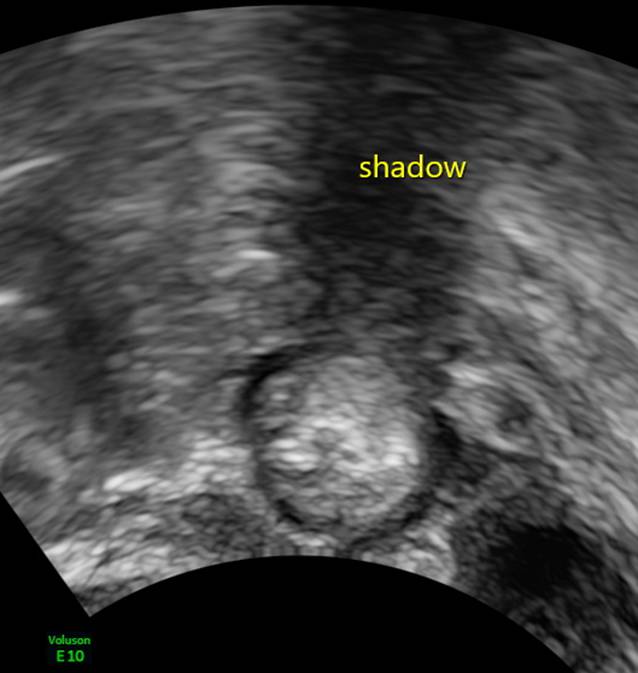

Als Nächstes ist auf akustische Schatten zu achten, die die Läsion allenfalls verursachen kann (Abb. 7). Schließlich muss das Vorhandensein von Aszites registriert werden (Abb. 8). Zu den Nichtultraschallwerten zählt zunächst das Alter der Patientin, dann muss eingegeben werden, ob die Untersuchung an einem gynäkologisch-onkologischen Schwerpunktzentrum stattfindet (Abb. 1).

Abb. 7

Beispiel für „shadowing“ distal eines 18 mm großen Dermoids. Diese Verschattungen ergeben in ADNEX „mildernde Umstände“ und senken das kalkulierte Risiko